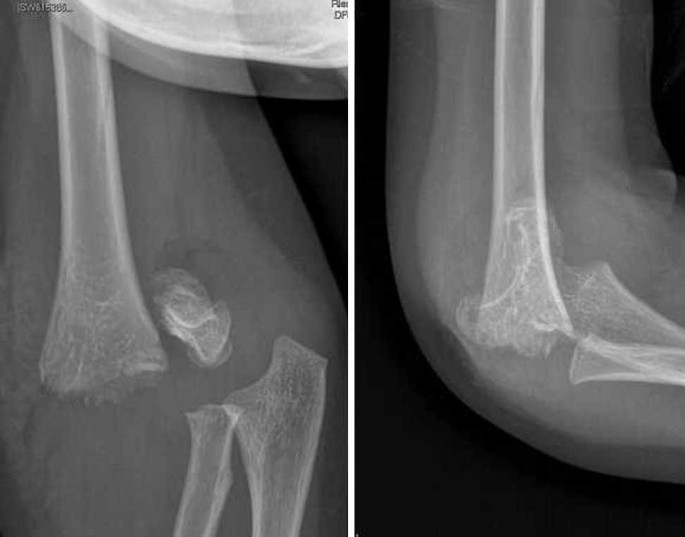

Frattura Sovracondiloidea Omero. Pseudoartrosi serrata Persistenza della rima di frattura. Nella maggior parte di. Radiografia in proiezione laterale di frattura sovracondiloidea dellomero Lomero distale si può fratturare sia per traumi diretti per cadute sul gomito che per traumi indiretti come la caduta sul palmo della mano a gomito esteso oppure per torsioni del gomito. Una frattura sopracondilare è una lesione allomero o osso superiore del braccio nel punto più stretto appena sopra il gomito.

Le rigidità post-traumatiche di gomito sono molto frequenti. La frattura è solitamente trasversale o obliqua e al di sopra dei condili e degli epicondili mediali e laterali. Una frattura dellomero sopracondilare è una frattura dellomero distale appena sopra larticolazione del gomito. Risultato definitivo 3 E stata accertata da Moore che tale affezione si instaura su un particolare terreno spasmofilo. Pseudoartrosi serrata Persistenza della rima di frattura. Essi sono spesso causati da una caduta su un gomito tesa o di un colpo diretto al gomito.

La regione sovracondiloidea è una sede particolarmente debole nellomero in via di sviluppo. Le fratture sovracondiloidee dellomero rappresentano la più comune lesione scheletrica della regione del gomito in traumatologia pediatrica con un picco massimo di in-cidenza tra i 5 ed i 7 anni ed una prevalenza nel sesso maschile e nel lato sx rapporto MF. FRATTURA DELLOSSO La frattura è il risultato di un sovraccarico singolo o multiplo dellosso che si verifica nella frazione di un millisecondo. La frattura dellomero provoca un dolore. Fratture e distacchi del massiccio condiloideo dellomero distale - Frattura sovracondiloidea. In tale sede quindi il diametro AP dellome-ro è limitato e ciò determina un punto di debolezza.

Fratture sovracondiloidee sono il più comune tipo di infortunio al braccio superiore nei bambini. La frattura è solitamente trasversale o obliqua e al di sopra dei condili e degli epicondili mediali e laterali. Essi sono spesso causati da una caduta su un gomito tesa o di un colpo diretto al gomito. In tale sede quindi il diametro AP dellome-ro è limitato e ciò determina un punto di debolezza. La frattura sovracondiloidea dellʼomero è la lesione più frequente del gomito nel bambino.

Frattura sovracondiloidea scomposta dell omero dx. Il lato sinistro risulta essere il più colpito. Frattura sovracondiloidea scomposta dell omero dx. Arteria omerale 3 Frattura sovracondiloidea dellomero. Radiografia in proiezione laterale di frattura sovracondiloidea dellomero Lomero distale si può fratturare sia per traumi diretti per cadute sul gomito che per traumi indiretti come la caduta sul palmo della mano a gomito esteso oppure per torsioni del gomito.

Lintervento chirurgico di artrolisi ha come scopo quello di migliorare l. La frattura è solitamente trasversale o obliqua e al di sopra dei condili e degli epicondili mediali e laterali. La frattura sovracondiloidea dellʼomero è la lesione più frequente del gomito nel bambino. Nelle fratture scomposte la riduzione a cielo chiuso e la fissazione per-cutanea con fili di Kirschner incrociati con paziente in posizione supina sul tavolo operatorio è una procedura ampiamente diffusa ed accettata. Fratture e distacchi del massiccio condiloideo dellomero distale Frattura sovracondiloidea.

Lesioni vascolo-nervose la frattura sovracondiloidea dellomero può provocare una lesione del nervo mediano che scorre estremamente vicino al tessuto osseo quindi anche una lieve scomposizione può venire a determinare uninterruzione di questo nervo PRECOCI - Sindrome di Volkmann. Lesioni vascolo-nervose la frattura sovracondiloidea dellomero può provocare una lesione del nervo mediano che scorre estremamente vicino al tessuto osseo quindi anche una lieve scomposizione può venire a determinare uninterruzione di questo nervo PRECOCI - Sindrome di Volkmann. Radiografia in proiezione laterale di frattura sovracondiloidea dellomero Lomero distale si può fratturare sia per traumi diretti per cadute sul gomito che per traumi indiretti come la caduta sul palmo della mano a gomito esteso oppure per torsioni del gomito. Con questa tecnica il. In tale sede quindi il diametro AP dellome-ro è limitato e ciò determina un punto di debolezza.

Lesioni vascolo-nervose la frattura sovracondiloidea dellomero può provocare una lesione del nervo mediano che scorre estremamente vicino al tessuto osseo quindi anche una lieve scomposizione può venire a determinare uninterruzione di questo nervo PRECOCI - Sindrome di Volkmann. Nelle fratture scomposte la riduzione a cielo chiuso e la fissazione per-cutanea con fili di Kirschner incrociati con paziente in posizione supina sul tavolo operatorio è una procedura ampiamente diffusa ed accettata. Le fratture sovracondiloidee dellomero rappresentano la più comune lesione scheletrica della regione del gomito in traumatologia pediatrica con un picco massimo di incidenza tra i 5 e i 7 anni e una distribuzione sostanzialmente sovrapponibile tra i due sessi. A causa di cadute accidentali infortuni sportivi o incidenti stradali tutte e tre le regioni di questo osso possono subire un trauma e fratturarsi. La regione sovracondiloidea è una sede particolarmente debole nellomero in via di sviluppo.